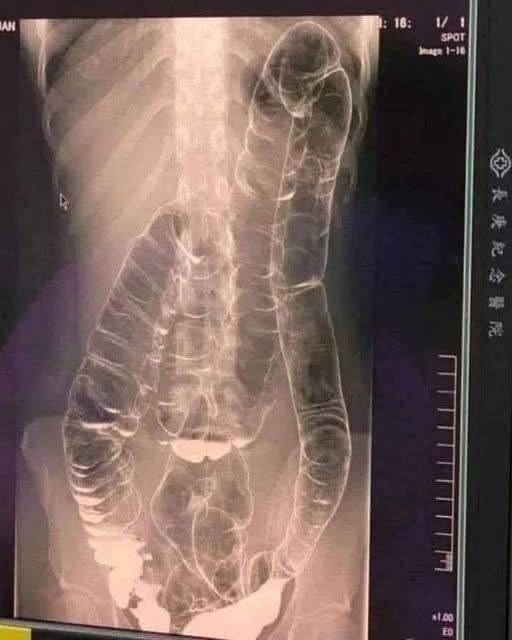

Entre los síntomas más habituales del estreñimiento se encuentran la sensación de evacuación incompleta, dolor o esfuerzo excesivo al defecar, hinchazón abdominal y una sensación constante de pesadez. Aunque muchas personas consideran que es un malestar del pasajero, lo cierto es que cuando se vuelve crónico, puede dar lugar a complicaciones graves como hemorroides , fisuras anales , impactación fecal (una acumulación tan severa de heces que bloquea el colon o el recto), e incluso puede contribuir a desarrollar megacolon tóxico , una condición potencialmente mortal. Además, algunos estudios han vinculado el estreñimiento crónico con un aumento del riesgo de cáncer colorrectal , aunque aún se requiere más evidencia científica para confirmarlo con certeza.